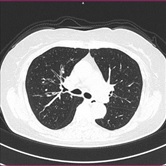

胸部CT 腹部CT

胸部CT画像               腹部CT画像